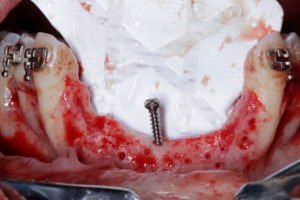

Um parafuso tipo tenda foi posicionado com a cabeça aproximadamente na altura dos picos ósseos residuais. A decorticalização foi feita, a membrana não reabsorvível de PTF-HD (Cytoplast 30×40 250) foi posicionada e fixada na região palatina, utilizando microparafusos autoperfurantes. O osso particulado (osso autógeno, dentina processada, matriz mineral bovina e LPRF) foi cuidadosamente posicionado e a membrana foi acomodada e fixada na região vestibular.

Houve precaução para que a membrana não tocasse os dentes adjacentes, seguido da proteção da membrana densa com membranas de LPRF. As suturas foram realizadas sem tensão usando monofilament 3.0 e 4.0 de teflon (Cytoplast). A radiografia periapical final mostra a magnitude da reconstrução.